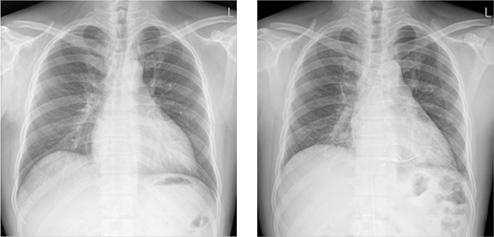

• 엡스타인 기형을 수술받지 않은 채 살아온 54세 환자의 수술 전(좌측)과

수술 후(우측) 흉부 X 선 사진 비교수술 후 심장의 크기가 감소하고 있습니다.